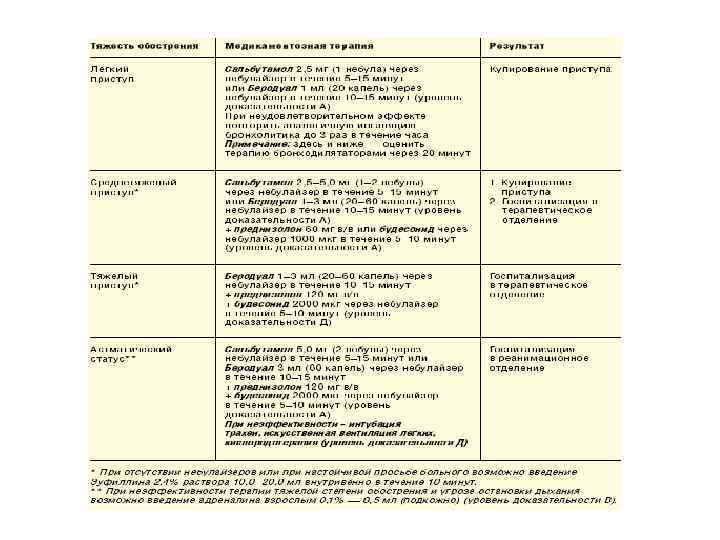

2. Степень тяжести течения (ступени): – – Ступень I – интермиттирующая астма (эпизодическая): симптомы - реже 1 раза в неделю; обострения заболевания короткие (от нескольких часов до нескольких дней); ночные симптомы менее 2 раз в месяц ; ОФВ 1 (ПСВ) >80% от нормы, суточные колебания < 20%. Ступень II - легкая персистирующая астма: симптомы проявляются от 1 раза в неделю до 1 раза в день; ночные симптомы возникают более 2 раз в месяц; обострения заболевания нарушают активность и сон; ОФВ 1 (ПСВ) >80% от нормы, суточные колебания 20 - 30%. Ступень III - персистирующая астма средней тяжести: ежедневные симптомы; обострения заболевания нарушают активность и сон; ночные симптомы возникают более 1 раз в неделю; необходим ежедневный прием бета – 2 агонистов короткого действия; ОФВ 1 (ПСВ) от 60 до 80% от нормы, суточные колебания более 30%. Ступень IY - тяжелая персистирующая астма: постоянные симптомы; частые обострения заболевания нарушают активность и сон; частые ночные симптомы; физическая активность ограничена, необходим ежедневный прием бета – 2 агонистов короткого действия; ОФВ 1 (ПСВ) < 60% от нормы, суточные колебания более 30%.

3. Фазы течения: – – – Фаза обострения. Фаза нестабильной ремиссии. Фаза стабильной ремиссии – не менее 2 лет полностью отсутствуют проявления заболевания 4. Осложнения: – – Астматический статус. Спонтанный пневмоторакс. Ателектаз легких. Беттолепсия – кратковременные обмороки во время пароксизма кашля в результате преходящей гипоксии мозга.